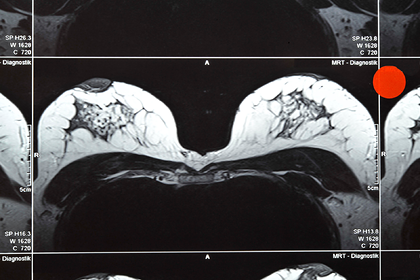

После душа она расчесывала 45-сантиметровую шевелюру, которая достигала низа ее груди. Она запустила пальцы в волосы и нащупала уплотнение под правой грудью. Шотландка обратилась к врачу. Обследования показали, что у нее рак груди третьей стадии.

До этого врачи удаляли ей 9-миллиметровую опухоль из груди, и шотландка была уверена, что окончательно победила рак. Оказалось, что заболевание вернулось. После того, как анализы показали, что у нее есть ген BRCA2, известный как ген рака груди, в январе Ларкин решилась на операцию по удалению молочной железы.